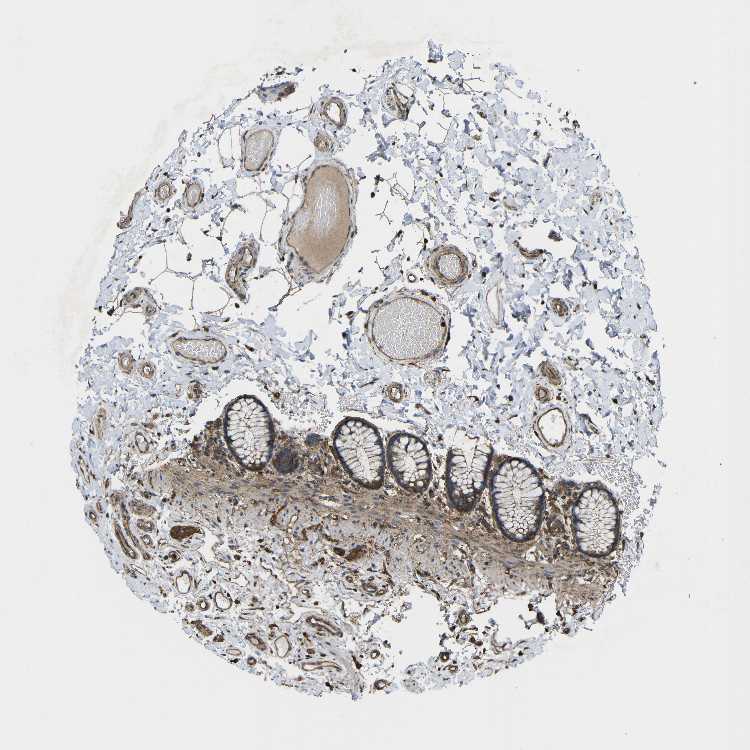

Antibody staining in the annotated cell types in the current human tissue is reported as not detected, low, medium, or high. This score is based on the staining intensity and fraction of stained cells.

Information about each individual sample is listed below, including gender, age, a tissue section image and estimated fractions of cell types. pTPM (transcripts per million) values give a quantification of the gene abundance which is comparable between different genes and samples.